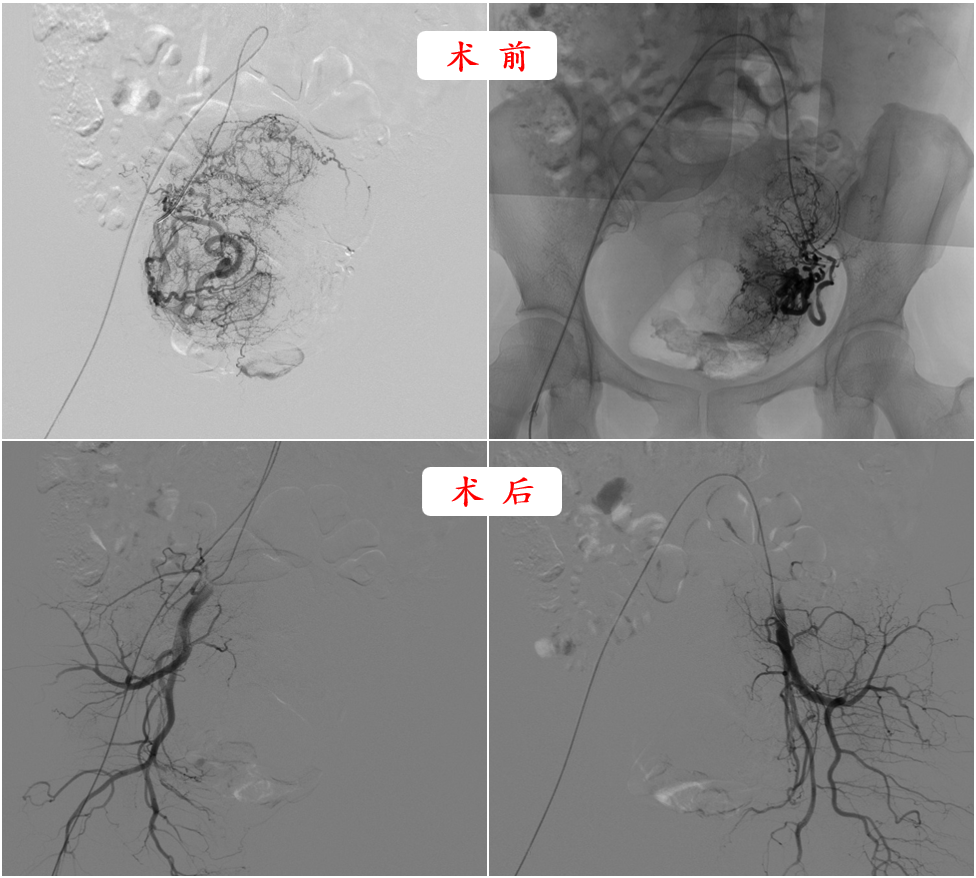

徐燕能详细向刘女士及家属讲解了治疗方案,刘女士等欣然接受。一切准备就绪后,徐燕能立即为刘女士实施了“子宫动脉造影+栓塞术”微创手术,术中通过股动脉穿刺将导管插入子宫动脉,然后注入栓塞物质,选择性阻断子宫肌瘤病灶的血液供应,整个手术过程大约60分钟,术后第三天,刘女士就顺利出院。

术后每月复查提示子宫肌瘤逐渐缩小,半年后子宫肌瘤从原来的9cm缩小到了2cm,然后刘女士就成功怀孕了,并生下一个健康可爱的儿子。当儿子两岁的时候,刘女士成功又怀上了第二胎。